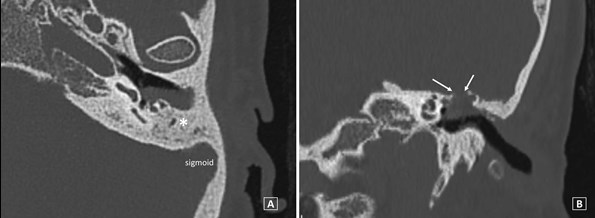

This patient had an iatrogenic dural defect with two previous attempts at reconstruction and was referred to our centre for definitive treatment. The patient had a very small, sclerotic mastoid with prominent sigmoid sinus restricting a transmastoid approach, and the defect was situated medially at the anterior attic (Figure 1).

Figure 1: Computed tomography showing the sclerotic left mastoid (*) and prominent sigmoid on the axial plane (A) and the bony defect and site of CSF leak (arrows) on coronal plane (B).